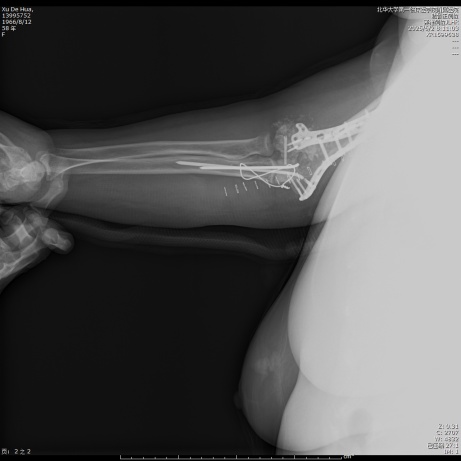

待麻醉生效后,患者取左侧卧位于手术台上,右上肢术区常规消毒,铺无菌单,贴皮肤保护膜。取右上臂中远段后正中入路,纵行切开一长约18.0 cm手术切口,依次切开皮肤、皮下,切开筋膜层,充分显露尺骨鹰嘴,将尺神经分离充分显露后予以保护,应用微型摆锯“V”形截骨尺骨鹰嘴,将尺骨鹰嘴连同肱三头肌腱剥离,湿盐水纱布保护,注意保护桡神经,暴露肱骨中远段,见肱骨中下段螺旋形骨折,分离短缩移位,肱骨滑车、肱骨小头、肱骨内外髁多处骨折线,分离旋转移位,局部骨质缺损,将肱骨中下段、肱骨滑车、肱骨小头、肱骨内外髁骨折复位,克氏针临时固定,后分别于右肱骨远折端内侧、后侧铺放2枚解剖型钢板,注意保护桡神经和尺神经,拧入数枚螺钉固定,C臂透视见钢板及螺钉长度及位置满意(见图2)。并于外髁骨缺损处植入3.0 g β-磷酸钙生物陶瓷不规则颗粒。将截断的尺骨鹰嘴复位后打入两根克氏针临时固定,并应用钢丝“8”字捆绑固定(见图3),活动肘关节,见骨折复位固定确实,关节无异响和绞索。后将尺神经松解前置,见神经松紧带适宜。后清点器械、纱布无误后,冲洗术区,彻底止血,术区留置负压引流管1枚,撒入盐酸万古霉素0.5 g及止血粉于切口内,预防感染及促进止血,应用可吸收性倒刺线2根逐层缝合肌层及皮下,一次性使用皮肤缝合器关闭切口,无菌敷料进行外包扎,石膏托固定肘关节于功能位(90˚屈曲),术毕。手术经过顺利,麻醉效果满意,术中出血量约1200 ml,给予输注ABO血型AB型Rh(D)阳性去白细胞悬浮红细胞2单位,过程中无明显输血不良反应,术后患者呈清醒状态安返病房。

Figure 3. Pre- and post-operative radiographs of double plate and screw internal fixation via the ulnar olecranon osteotomy approach and open reduction

3. 经尺骨鹰嘴截骨入路切开复位双钢板螺钉内固定手术前后X线片